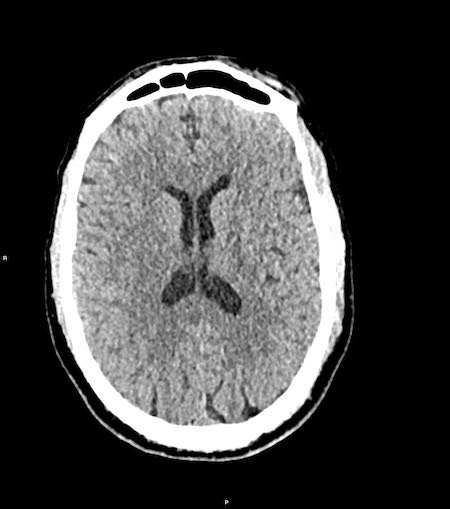

Bệnh nhân nam 46 tuổi bị chấn thương năng lượng cao khi đi xe máy.

Điểm EMV ban đầu là 2-5-3 và đồng tử hai bên giãn không phản xạ ánh sáng.

Hình ảnh CT

- Xuất huyết dạng chấm ở cả hai thùy trán.

- Gãy xương Le Fort II hai bên.